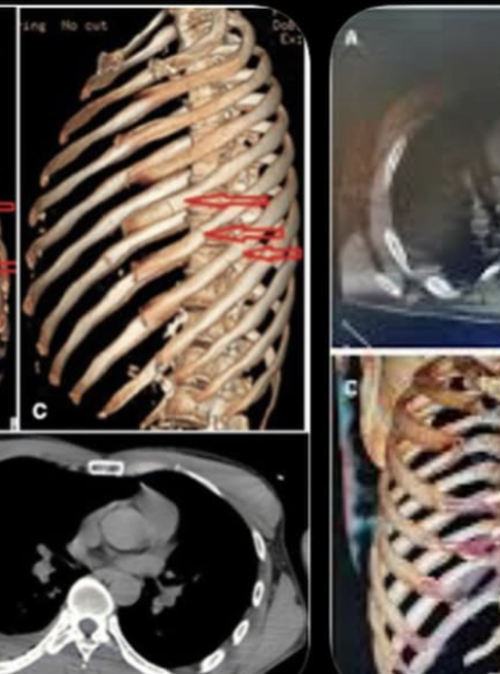

El hijo de Rick Harrison con quien comparte en el famoso reality sufrió 11 fracturas en la caja torácica y lleva varias noches internado.

"Estoy bastante mal, pero estoy bien, las barras de choque son geniales. Tres noches en el hospital, once fracturas en la caja torácica. Haré un episodio en @theCoreyHarrisonshow. Lo siento, papá. parece que me estoy perdiendo tu boda" dijo, a pocos días de la celebración de su padre.

El personaje de 42 años mostró sus radiografías donde se aprecia cómo fueron tratadas sus heridas, por el momento se encuentra en recuperación.